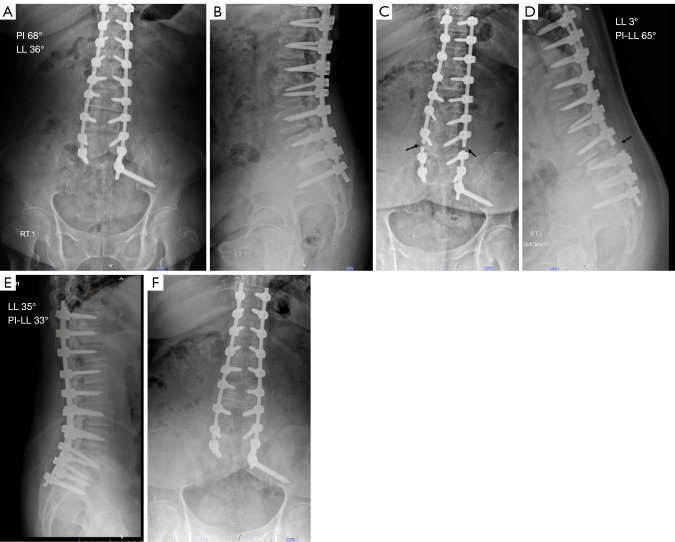

Abstract Image